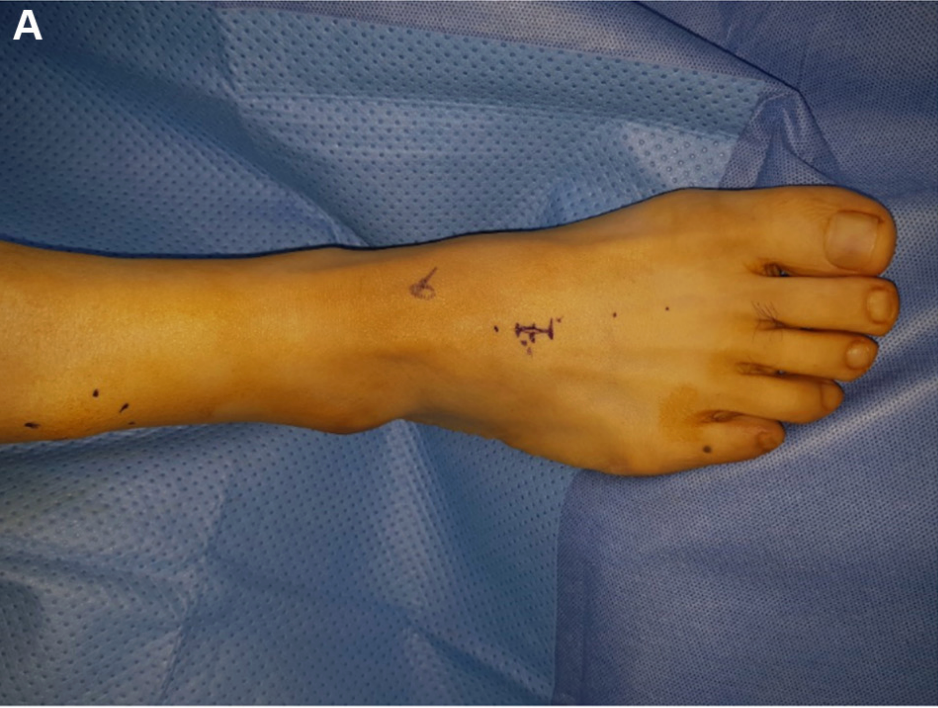

▲图示背侧皮肤切口。